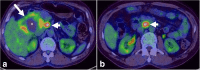

Malignancies of the biliary tract include cholangiocarcinoma, gallbladder cancers and carcinoma of the ampulla of Vater. Biliary tract adenocarcinomas are the second most common primary hepatobiliary cancer. Due to their slow growing nature, non-specific and late symptomatology, these malignancies are often diagnosed in advanced stages with poor prognosis. Apart from incidental discovery of gall bladder carcinoma upon cholecystectomy, early stage biliary tract cancers are now detected with computed tomography (CT) and magnetic resonance imaging (MRI) with magnetic resonance cholangiopancreatography (MRCP). Accurate characterization and staging of these indolent cancers will determine outcome as majority of the patients' are inoperable at the time of presentation. Ultrasound is useful for initial evaluation of the biliary tract and gallbladder masses and in determining the next suitable modality for further evaluation. Multimodality imaging plays an integral role in the management of the biliary tract malignancies. The imaging techniques most useful are MRI with MRCP, endoscopic retrograde cholangiopancreatography (ERCP), endoscopic ultrasound (EUS) and positron emission tomography (PET). In this review we will discuss epidemiology and the role of imaging in detection, characterization and management of the biliary tract malignancies under the three broad categories of cholangiocarcinomas (intra- and extrahepatic), gallbladder cancers and ampullary carcinomas.